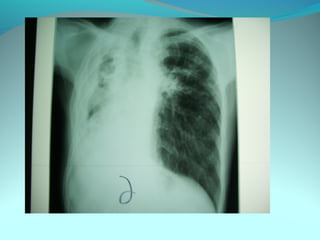

Clarté retroclaviculaire gauche d 3cm de diam

entouré d’une paroi de 1cm d’epaisseur

La limite interne se confend avec le mediastin

Les autre limites sont nette

DIAGNOSTIC

Caverne tuberculeuse gauche